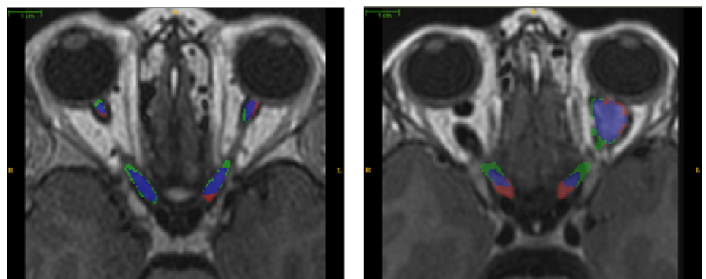

After Institutional Review Board approval, 15 pediatric MRI scans with healthy AVPs and 6 with OPG were acquired for this study. The acquired data were T1 weighted cube with Gadolinium contrast enhancement having spatial resolution between 0.39×0.39×0.6mm30.390.390.6superscriptmm30.39\times 0.39\times 0.6\text{mm}^{3} to 0.47×0.47×0.6mm30.470.470.6superscriptmm30.47\times 0.47\times 0.6\text{mm}^{3}. The manual ground truth for optic pathway segmentation was created by an expert neuro-radiologist and an expert neuro-ophthalmologist. During the training stage, the dataset was affinely registered to a randomly chosen reference image using a two-stage hierarchical approach: first by optimizing the registration parameters for the entire brain and later by optimizing over the region of interest around the optic nerve. The surfaces for each training instance were computed using the tetrahedral mesh generation approach followed by point set registration to the reference surface. Based on our training set, optimal number of partitions were found to be 12. Three hierarchical scales for shape model and appearance were used. The refinement model was learned on-the-fly from the initial segmentation using a patch of size 11×11×1111111111\times 11\times 11 voxels at the coarsest level. The normalized derivative, the tissue intensity probability, and the tubular structure probability were used together as a unified feature set of size 33 to train the refinement model. To learn the sparse dictionary, co-occurrence features were extracted with an offset of 1 and four directions (00, π4𝜋4\frac{\pi}{4}, π2𝜋2\frac{\pi}{2}, 3π43𝜋4\frac{3\pi}{4}). The co-occurrence features presented in Section 2.3 are then calculated for each direction. During the testing stage, the test image was first registered to the randomly selected reference set followed by automatic overlapping partitioning. The mean shape of the training set was used to initialize the shape model. Fig. 3 shows the qualitative results of PAScAL against the ground truth manual segmentation.

Refer to caption

Figure 3: Segmentation results for a representative healthy (left) and OPG case (right). Blue label shows overlap area of manual and automated segmentation, red label shows the manual label while the green label shows the automated segmentation.